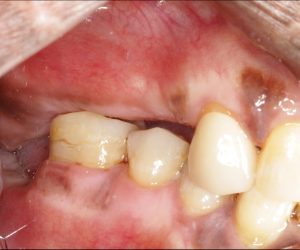

This patient wants implants. We just finished treating her periodontal disease and she is ready for the next phase, however, she has severe bite collapse. In addition, she has uneven ridge in the upper anterior, which would make it challenging esthetically. I asked her dentist to make her a partial denture but the patient kept going back…

You’re right, the bite collapse and the uneven ridge in the upper anterior make things tricky. It’s understandable the patient struggled with the partial denture, especially with the adjustments.